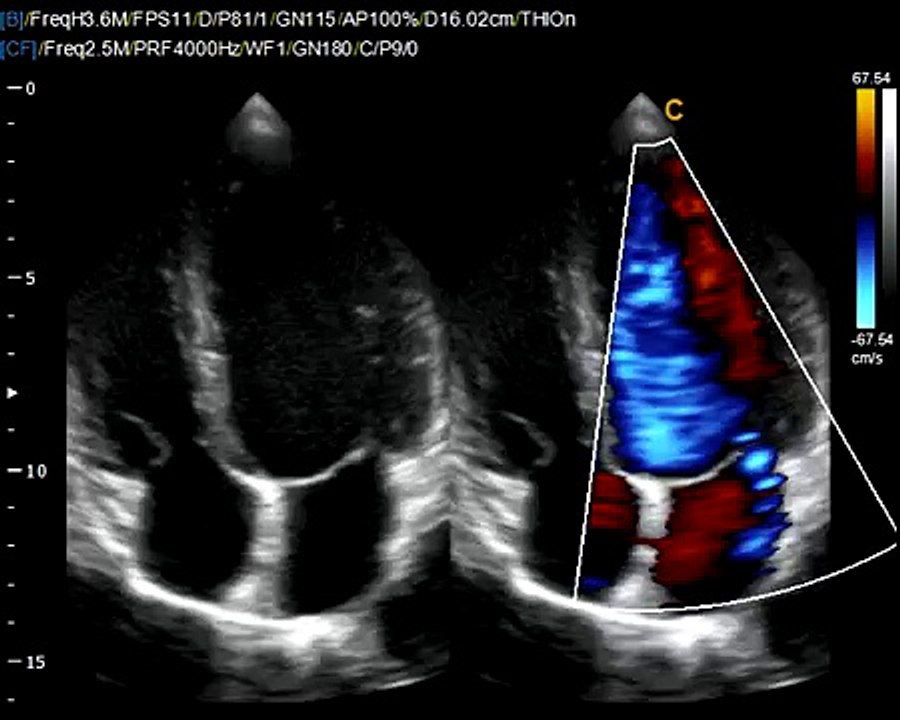

CASIS: CArdiac Simulation & Imaging Software, Quetigny

Cet été, partez à la découverte des entreprises innovantes en Bourgogne-Franche-Comté, c'est Made In Bourgogne Franche Comté!<br /><br />Découvrez CASIS: CArdiac Simulation & Imaging Software, Quetigny <br /><br />Made In Franche Comté, le dossier complet, c'est ICI ➡https://bit.ly/2HGUek2